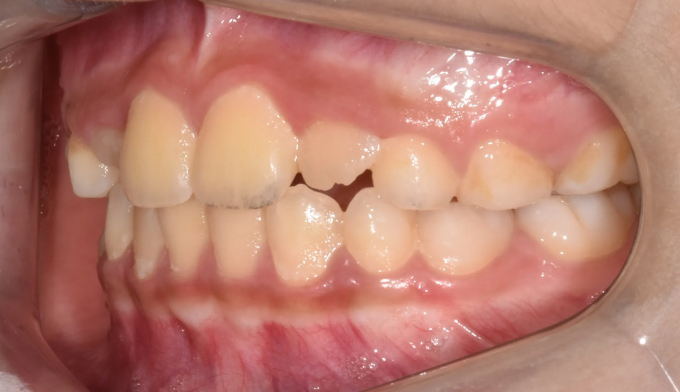

4개월간의 장치 착용으로 앞니가 정상적인 교합으로 형성되었고 이와 더불어 안모도 개선되었습니다.

하지만 반대교합이었던 아이들의 경우 아래턱의 성장을 주기적으로 관찰하여야합니다.

특히 급격한 성장기에 도달하게 되면 아래턱도 함께 자라는 경우가 있기 때문에 정기적인 검사가 필요합니다.